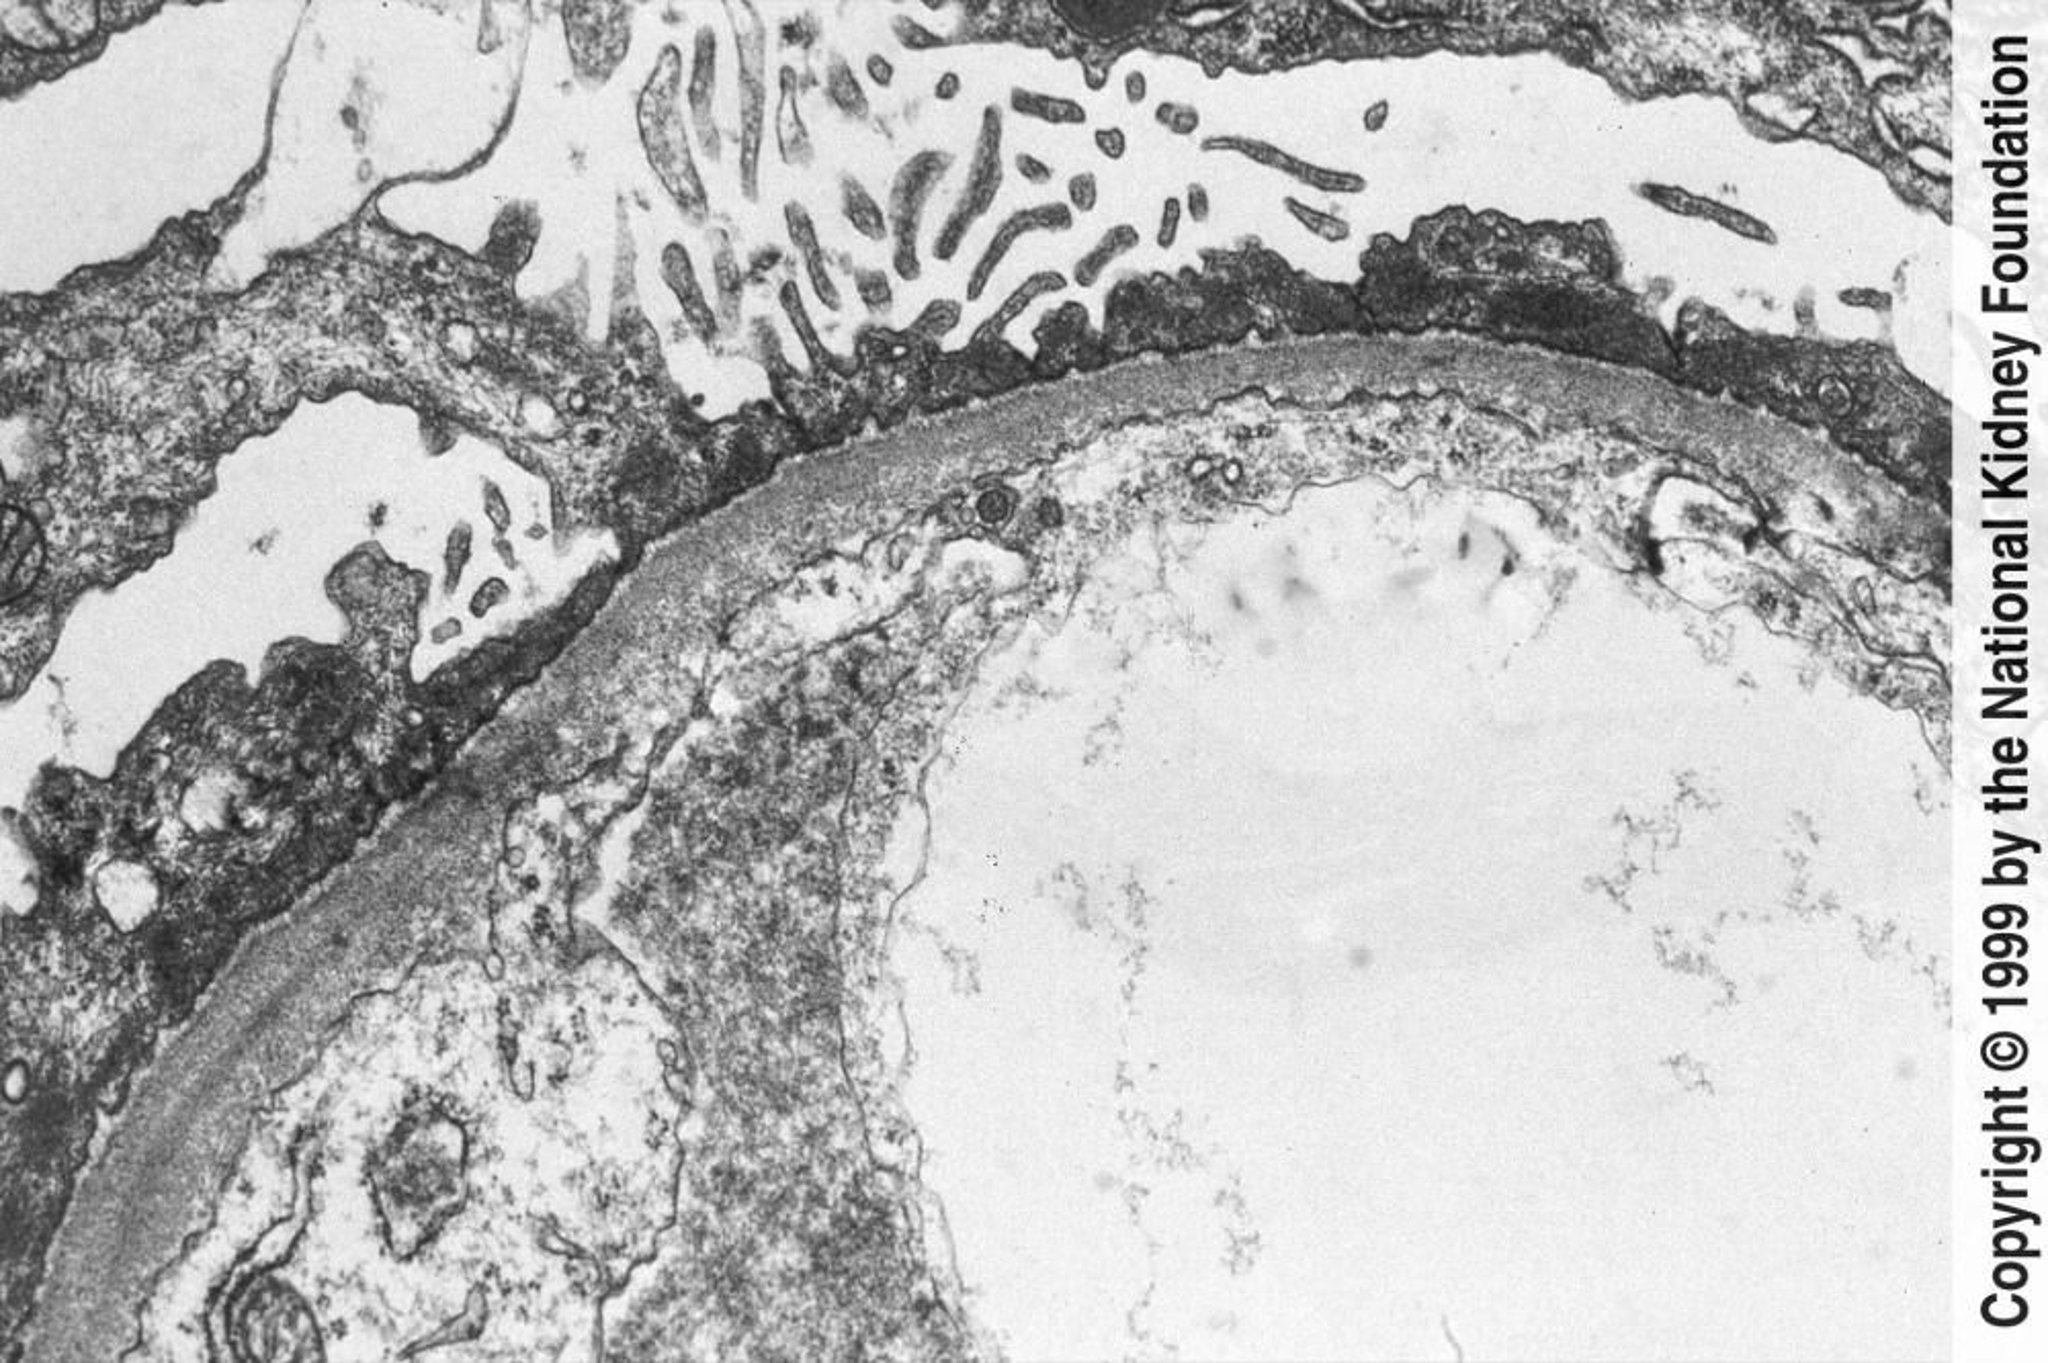

微小変化群

透過型電子顕微鏡で,足突起のびまん性の消失が観察できる(800倍)。

Image provided by Agnes Fogo, MD, and the American Journal of Kidney Diseases' Atlas of Renal Pathology (see www.ajkd.org).